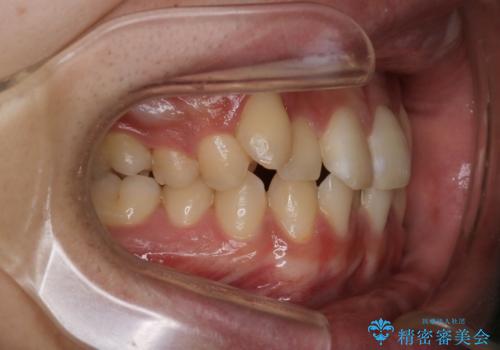

【クリア装置】八重歯とがたつきを綺麗に

- 上の八重歯と下の歯のがたつきを主訴に来院されました。

矯正検査の結果、抜歯はせずに

臼歯を遠心移動させ、歯列をワイヤーで整えることでスペースを確保し、IPR(歯と歯の間を削る処置)を加えて歯並びを綺麗にする治療計画を立てました。

気にされていた八重歯とがたつきが綺麗に改善されました。